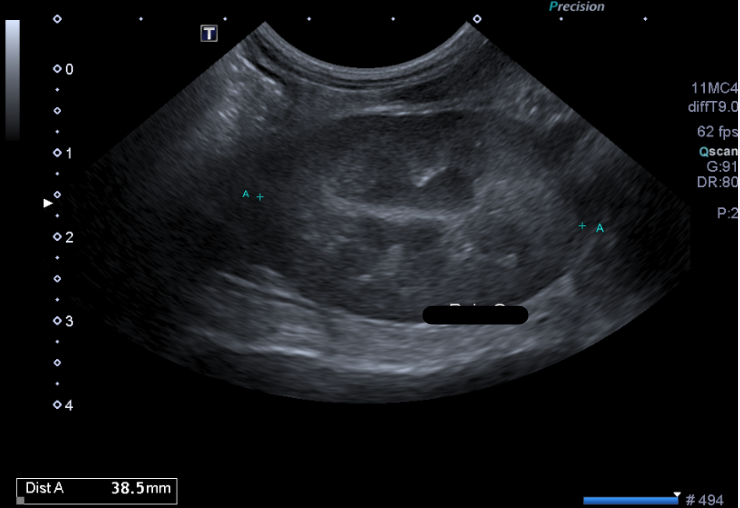

6- De quel organe s’agit-il ? Précisez G ou D et le plan de coupe réalisé

A - Le Rein Gauche en coupe transversale

B - Le Rein Droit en coupe transversale

C - Le Rein Gauche en coupe longitudinale

D - Le Rein Droit en coupe longitudinale

E - La Surrénale droite en coupe transversale

7 - En sachant que l'autre rein présente le même aspect échographique, et qu'ils mesurent tous les deux 3,5 cm de long, vous pouvez conclure :

A - Absence d'anomalie échographique visible

B - Nephromégalie bilatérale

C - Dilatation de la cavité pyélique

D - Signes échographiques en faveur d'une néphrite tubule-interstitielle

E - Signes échographiques en faveur d'une glomerulonephrite

Question 6 : Réponse C

Question 7 : Réponse A